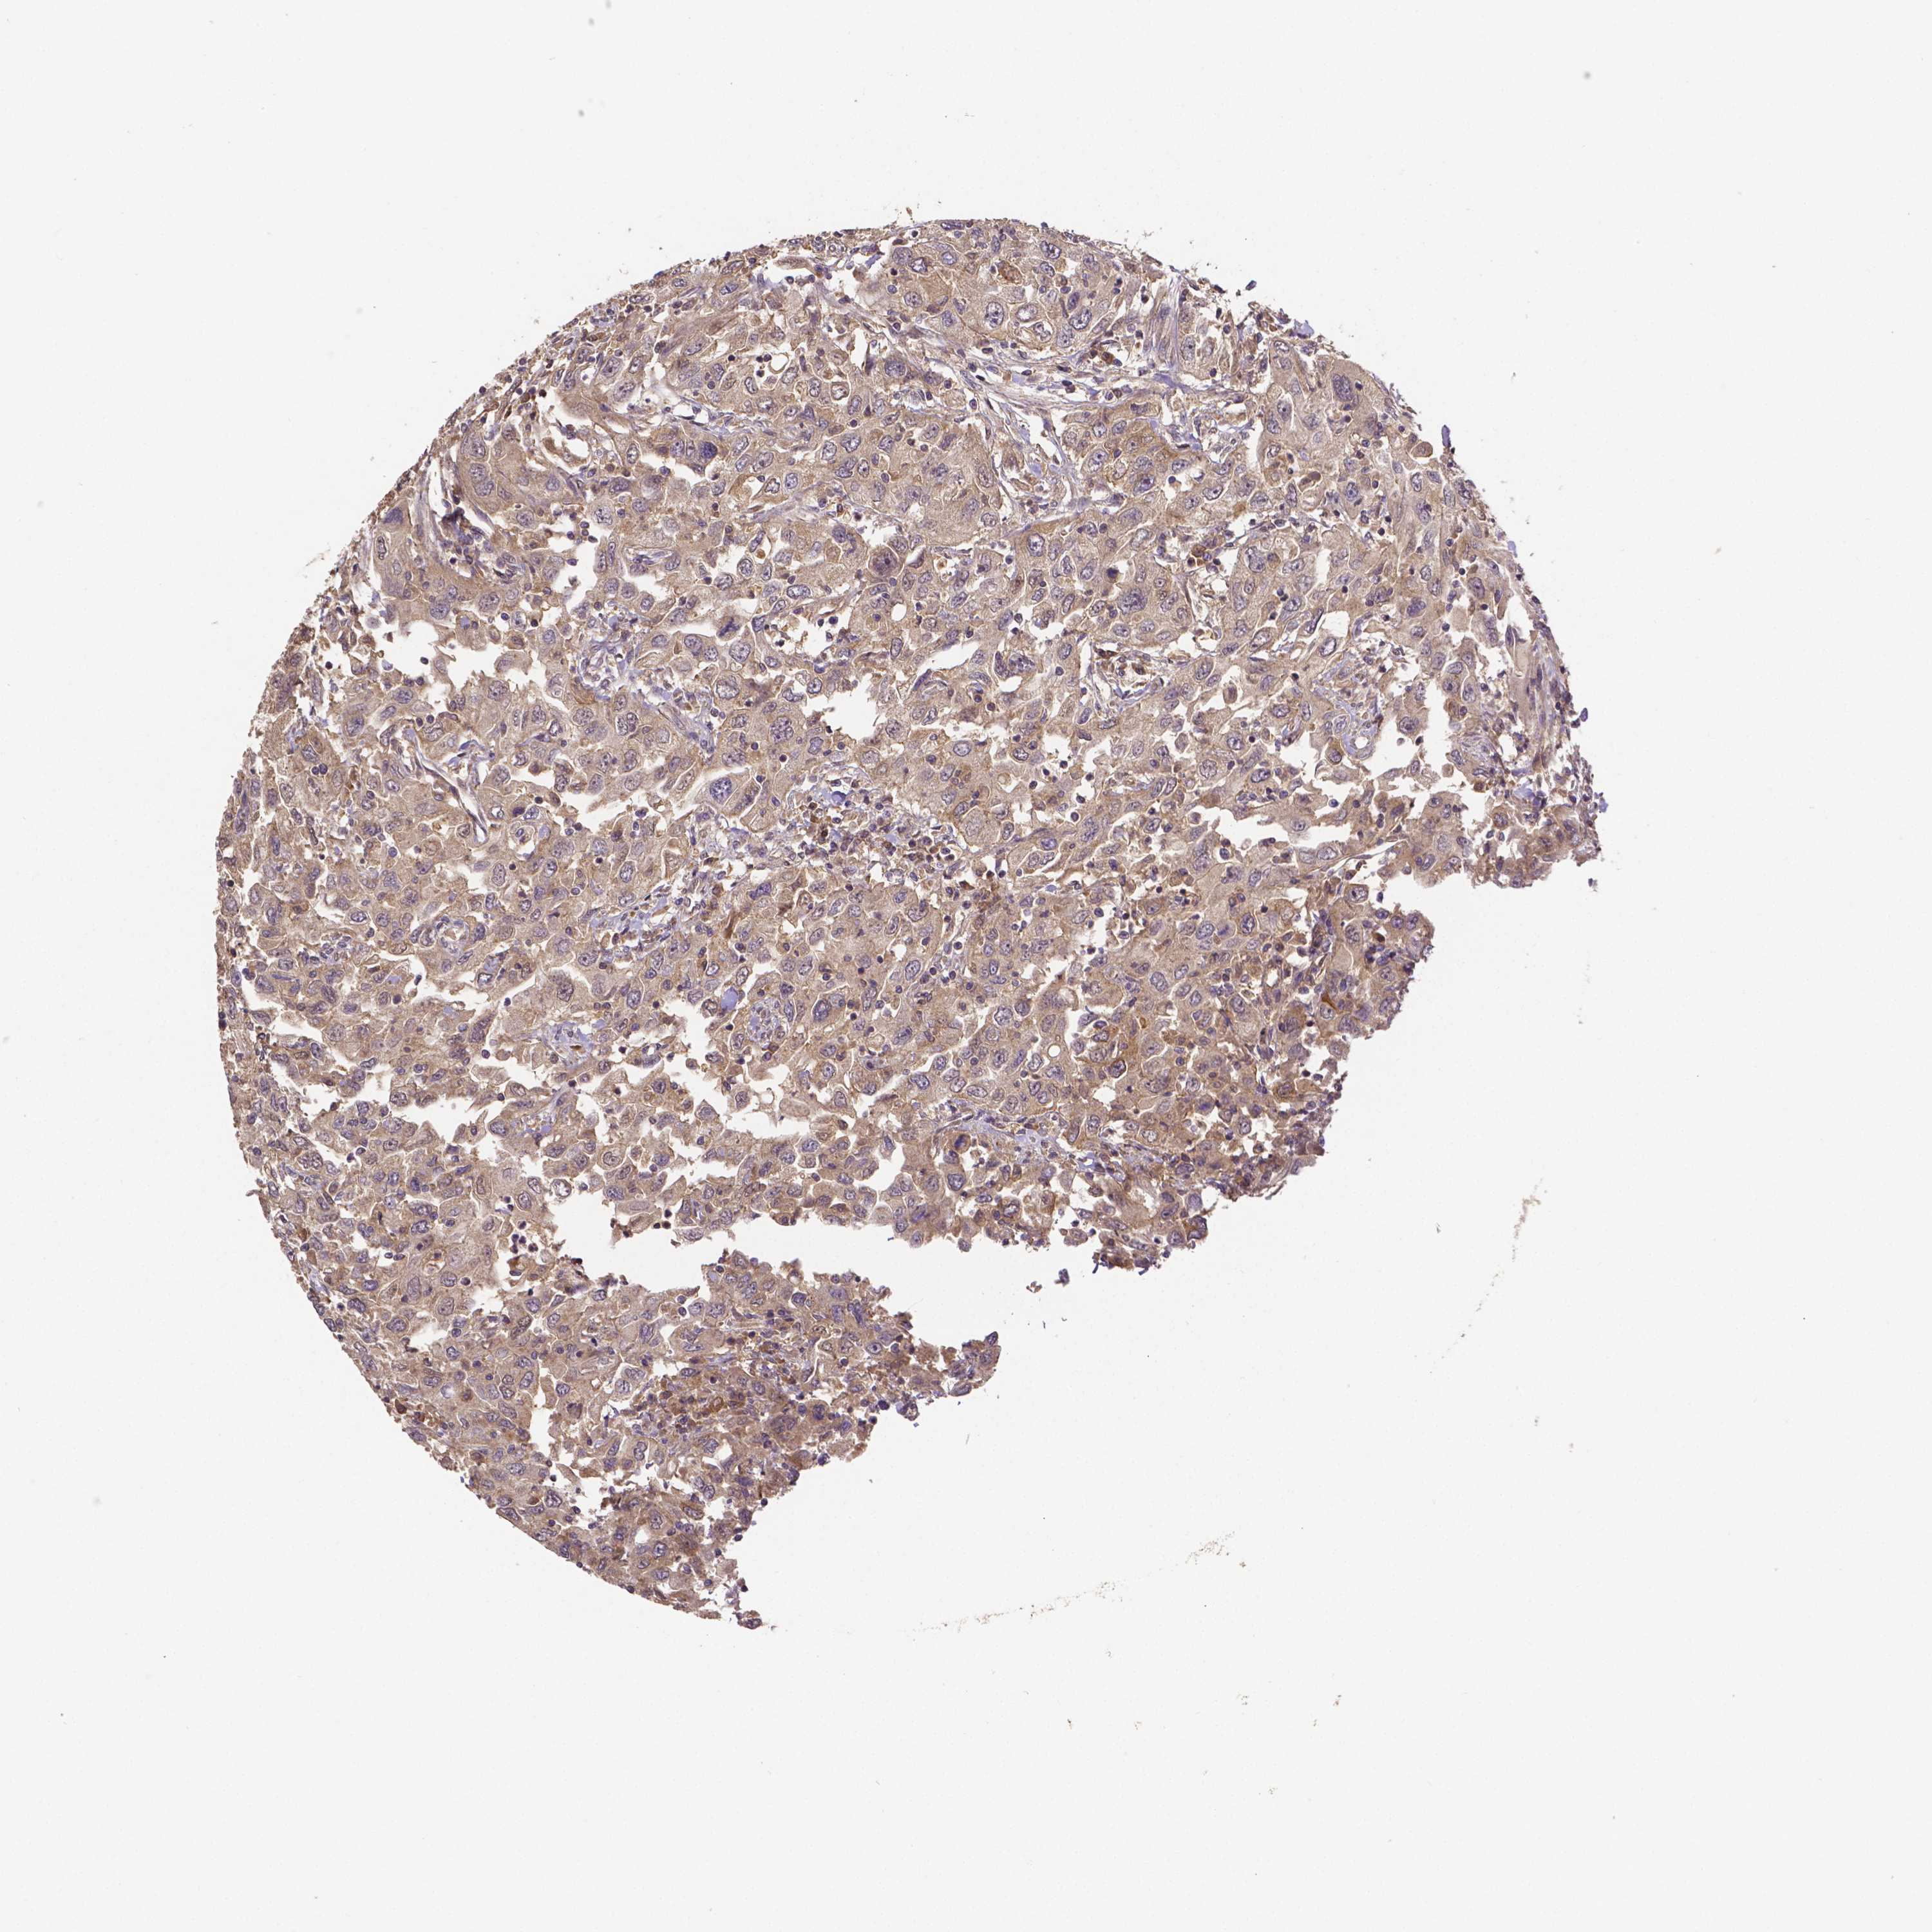

UROTHELIAL CANCER - Protein expressioni

A mouse-over function shows sample information and annotation data. Click on an image to view it in a full screen mode. Samples can be filtered based on level of antibody staining by selecting one or several of the following categories: high, medium, low and not detected. The assay and annotation is described here.

Note that samples used for immunohistochemistry by the Human Protein Atlas do not correspond to samples in the TCGA dataset.

Antibody stainingi

Antibody staining in the annotated cell types in the current human tissue is reported as not detected, low, medium, or high, based on conventional immunohistochemistry profiling in selected tissues. This score is based on the combination of the staining intensity and fraction of stained cells.

Each image is clickable and will lead to virtual microscopy that enables deeper exploration of all samples and also displays staining intensity scores, fraction scores and subcellular localization as well as patient and tissue information for each sample.

Antibody HPA065983

Antibody HPA071879

Staining

High

Medium

Low

Not detected

Intensity

Strong

Moderate

Weak

Negative

Quantity

>75%

75%-25%

<25%

None

Location

Nuclear

Cytoplasmic/membranous

Cytoplasmic/membranous,nuclear

Urothelial carcinoma, High grade

Urothelial carcinoma, Low grade